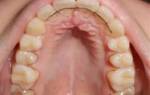

Грибок ротовой полости симптомы

В случаях, когда во рту нарушается щелочной баланс и преобладает кислая среда, Кандида начинает активно размножаться. В процессе жизнедеятельности этих микроорганизмов выделяются особые ферменты, они поражают слизистую оболочку, вызывая микоз (кандидоз, молочница). Чаще всего локализуются на внутренней стороне щек, на губах, небе, на языке, деснах.

Первый признак микоза – наличие белого налета на слизистых, при попытке удалять их, образуются кровоточащие ранки. Внешне налет напоминает творог или свернувшееся молоко.